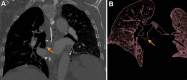

As lung transplantation has become the most effective definitive treatment option for end-stage chronic respiratory diseases, yearly rates of this surgery have been steadily increasing. Despite improvement in surgical techniques and medical management of transplant recipients, complications from lung transplantation are a major cause of morbidity and mortality. Some of these complications can be classified on the basis of the time they typically occur after lung transplantation, while others may occur at any time. Imaging studies, in conjunction with clinical and laboratory evaluation, are key components in diagnosing and monitoring these conditions. Therefore, radiologists play a critical role in recognizing and communicating findings suggestive of lung transplantation complications. A description of imaging features of the most common lung transplantation complications, including surgical, medical, immunologic, and infectious complications, as well as an update on their management, will be reviewed here. Keywords: Pulmonary, Thorax, Surgery, Transplantation Supplemental material is available for this article. © RSNA, 2021.